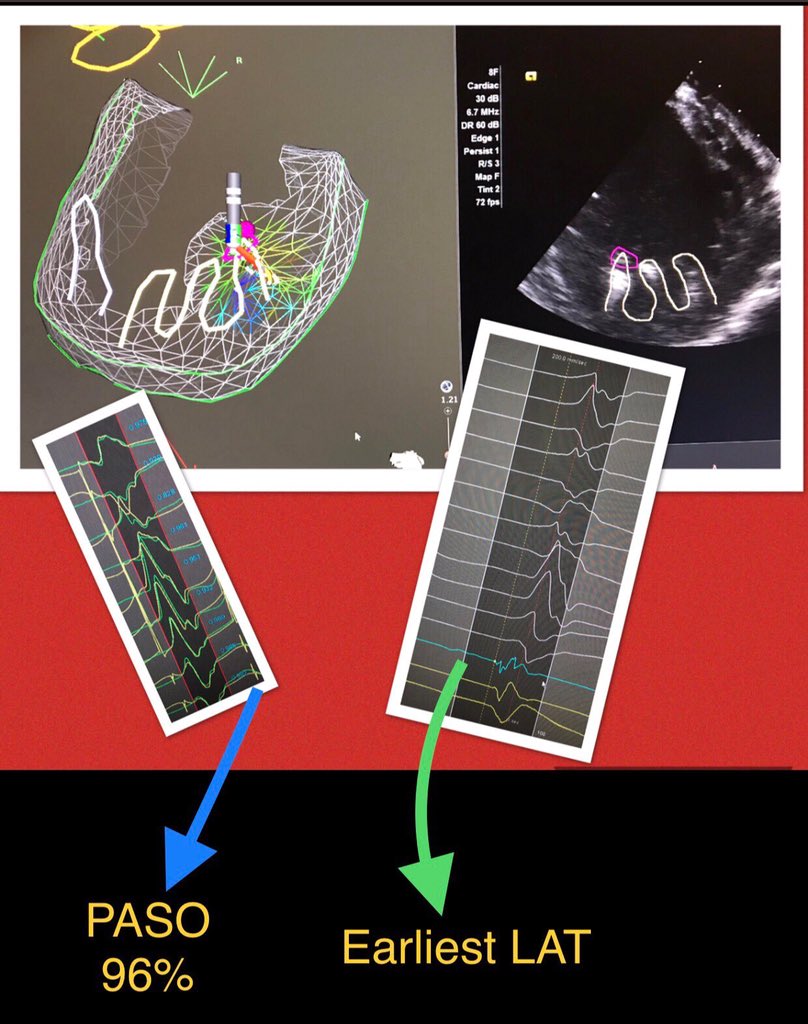

Amazing PAP PVC at NYP Columbia. contours of calcification on the PAP were drawn (pink tag). Pace match of 96% on that spot and 25ms early to onset QRS. Thanks for amazing case @kevivek

#ablatePVC #safensound #cartosound#oneburdndone